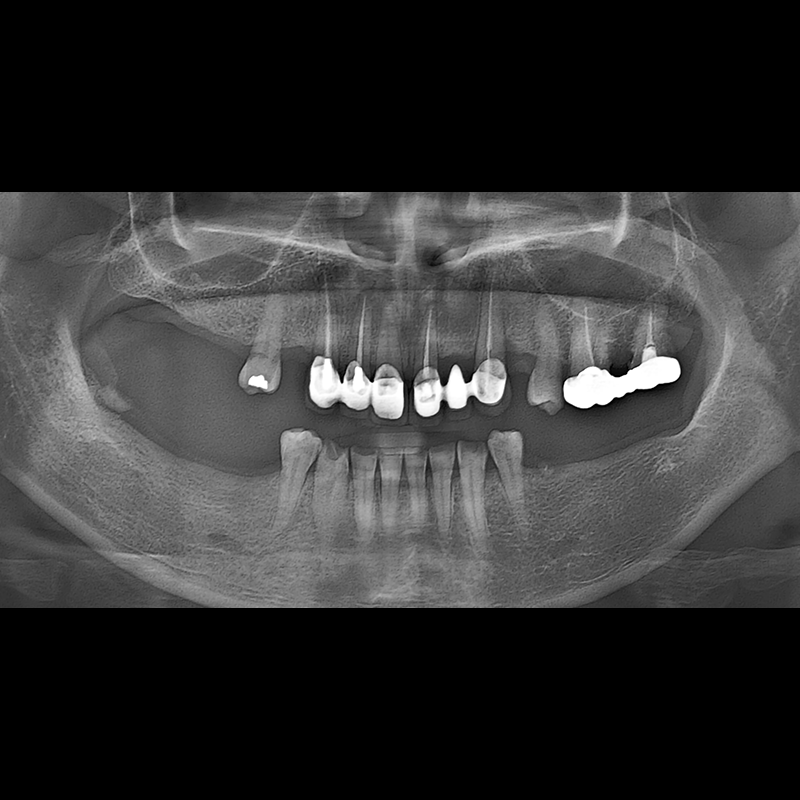

IMPLANT

BEFORE AFTER